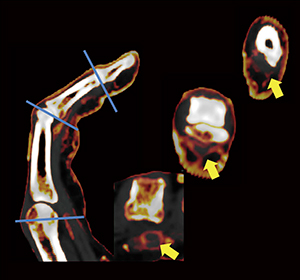

DECTによるヨードマップ画像の利点としては,PsA好発部位であるDIPの画像を鮮明に各指で評価が可能なことである。図2のように,5指すべてに高解像度の矢状断画像を作成でき,炎症の診断が可能である。また,変型が強い関節でも,各関節に対応した横断像を作成して診断することができる(図3)。それによって,PsAの診断がより正確になり,視覚的に治療評価が可能となった。

図3 変形が強い関節に対するDECTヨードマップ横断像による評価

79歳,男性。第3指屈筋腱の複数の腱鞘輪状部pulley(↑)に相当して腱鞘炎を認める。